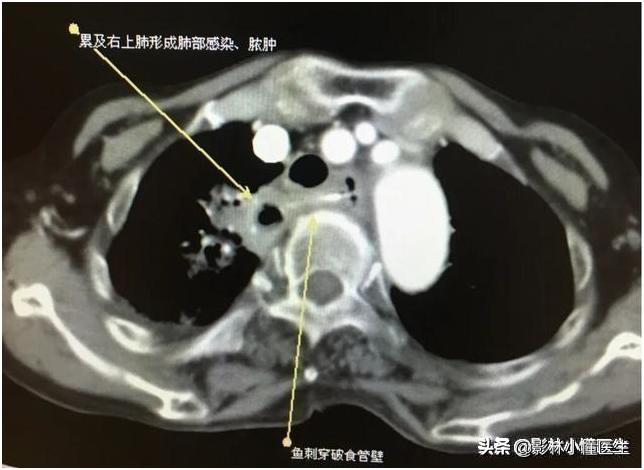

例1

食管穿孔继发纵隔及肺部感染;纵隔感染位置深,治疗困难大,部分患者发生脓毒血症,威胁生命。